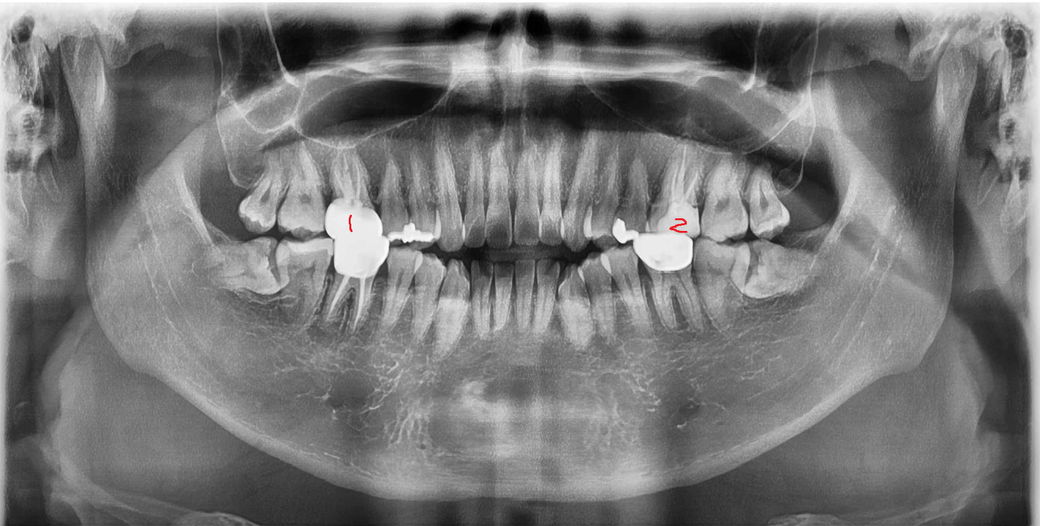

임플란트 하는거 말고는 답이 없을까요?

- 3월 말에 1~2년전 신경치료를 했던 1번 치아 통증이 심해서

다니던 병원에 갔었는데

1번치아 통증 느껴지는 상태

(가만히 있어도 통증이 가끔씩 느껴짐

뜨거운 물 먹을때나 자려고 누워있거나 통증이 느껴짐

1번치아 아래쪽치아랑 맞닿아서 꾹 눌러보면 통증 느껴짐

이 닦아도 개운하지가 않고 아래 크라운은 매끄러운 느낌인데 1번 크라운은 거친느낌? 뭔가 쓴게 새어나오는 느낌같은게 들어요)

• 1번 째 사진